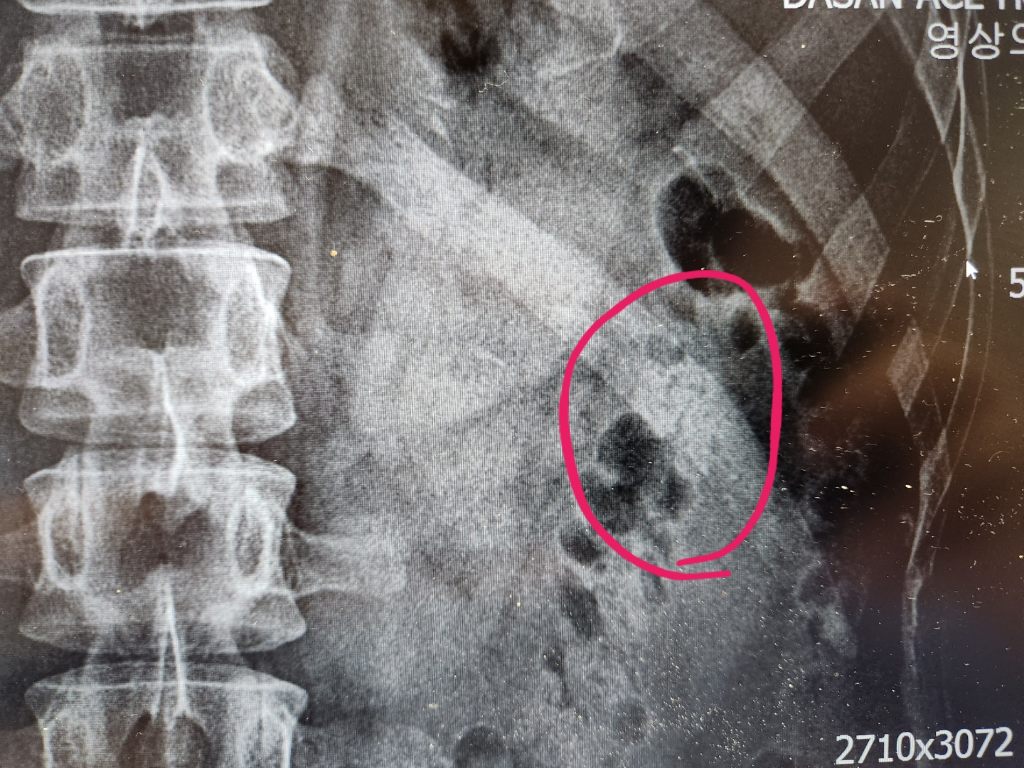

갈비뼈에 금이 가거나 골절이 생기면 생각보다 일상 불편이 큽니다. 팔이나 다리처럼 깁스를 해서 완전히 고정할 수 있는 부위가 아니기 때문에, 통증을 버티면서 숨 쉬고 기침하고 잠자는 모든 과정이 힘들어질 수 있습니다. 특히 갈비뼈 손상은 단순히 “시간이 지나면 낫는다”로 끝나는 문제가 아니라, 통증 조절이 제대로 되지 않으면 깊게 숨을 쉬지 못해 폐 합병증 위험까지 커질 수 있다는 점이 중요합니다. 실제로 갈비뼈 손상은 대부분 자연 치유가 가능하지만, 회복 속도를 좌우하는 핵심은 무리한 민간요법보다 통증 관리, 호흡 유지, 적절한 활동 조절, 균형 잡힌 영양 섭취에 있습니다.

갈비뼈에 금이 가면 가장 먼저 나타나는 것은 국소적인 통증입니다. 가만히 있을 때보다 몸을 비틀거나, 기침하거나, 재채기하거나, 깊게 숨을 들이마실 때 통증이 확연히 심해지는 경우가 많습니다. 눌렀을 때 특정 부위가 유난히 아프고, 자세를 바꾸거나 침대에서 일어날 때 찌르는 듯한 통증이 반복되면 갈비뼈 손상을 의심할 수 있습니다. 피부 멍, 압통, 붓기, 드물게는 ‘딱’ 하는 느낌이나 소리를 경험하는 사람도 있습니다. 다만 증상만으로 단순 타박상과 미세 골절을 완전히 구분하기는 어렵고, 외상 강도가 컸거나 고령자, 기저 폐질환자, 골다공증 위험군이라면 더 신중하게 봐야 합니다.

갈비뼈 골절은 대개 자연 치유가 가능하며, 일반적인 회복 기간은 수 주 정도로 안내되는 경우가 많습니다. 다만 ‘몇 주면 무조건 끝난다’고 단정하기는 어렵습니다. 미세 골절인지, 다발성 골절인지, 연령과 기저질환이 어떤지, 통증 조절이 잘 되는지에 따라 회복 체감 속도는 차이가 큽니다. 어떤 사람은 3주 전후부터 일상 기능이 꽤 회복되지만, 어떤 사람은 6주 이상 통증이 남기도 합니다. 중요한 것은 통증이 줄어드는 속도와 함께 호흡 상태가 안정적인지 보는 것입니다. 통증 자체보다 숨차거나 열이 나는 경우는 경과 관찰만으로 넘기지 않는 편이 안전합니다.